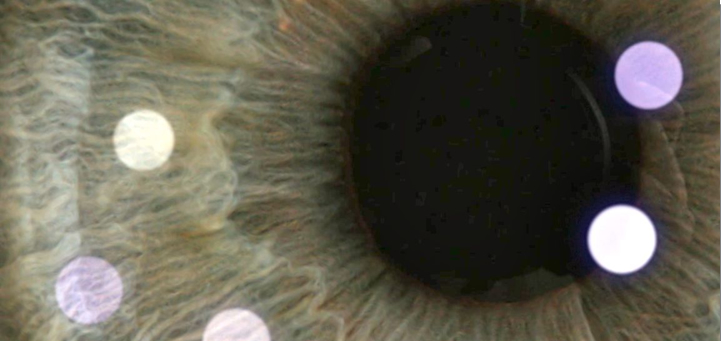

- Estudio corneal paquimétrico y topográfico normal.